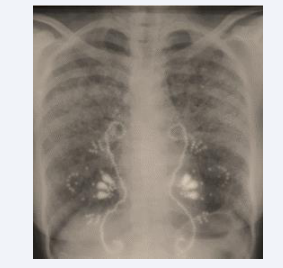

The patient is a 38-year-old black woman with no significant medical habits or history aside from cervical lymph node tuberculosis diagnosed at the age of 12, confirmed histologically by a tuberculoid granuloma with caseous necrosis. She reported no recent contact with tuberculosis in her surroundings and had no other associated pathologies. The onset of her illness dates back six months, marked by the gradual appearance of intermittent dry cough and exertional dyspnea, without hemoptysis, chest pain, or other associated extra pulmonary symptoms. These symptoms evolved in a context of febrile sensations, night sweats, and a general health decline characterized by asthenia, anorexia, and unquantified weight loss. The patient consulted a pulmonologist who ordered a frontal chest X-ray and an Interferon-Gamma Release Assay (IGRA), which tested positive. Based on the radioclinical data, a multidisciplinary decision concluded a diagnosis of pulmonary tuberculosis, and a six- month anti-tuberculous treatment was initiated. After 1.5 months of treatment, the clinical course showed slight improvement with regression of functional symptoms and a weight gain of 2 kg (Figure 1).

Figure 1 Chest X-ray after 1.5 months of anti-tuberculous treatment.

However, at the end of the six-month anti-tuberculous treatment, the patient experienced clinical worsening with dyspnea progressing to Mmrc stage III, profound anxiety, and radiological deterioration. A follow-up chest X-ray revealed the presence of diffuse bilateral micronodules (Figure 2).

Figure 2 Chest X-ray after 6 months of anti-tuberculous treatment showing diffuse bilateral micronodule.